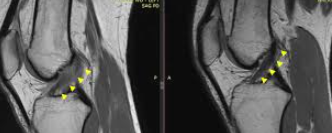

이 치료법은 환자의 골반에서 골수 60cc를 채취한 후 원심분리기로 분리하여 약 3cc의 농축된 줄기세포를 무릎에 주사하는 방식입니다. 마취나 절개가 필요 없어 당일 퇴원이 가능하며, 치료 후 바로 일상생활로 복귀할 수 있어 편의성이 높습니다.